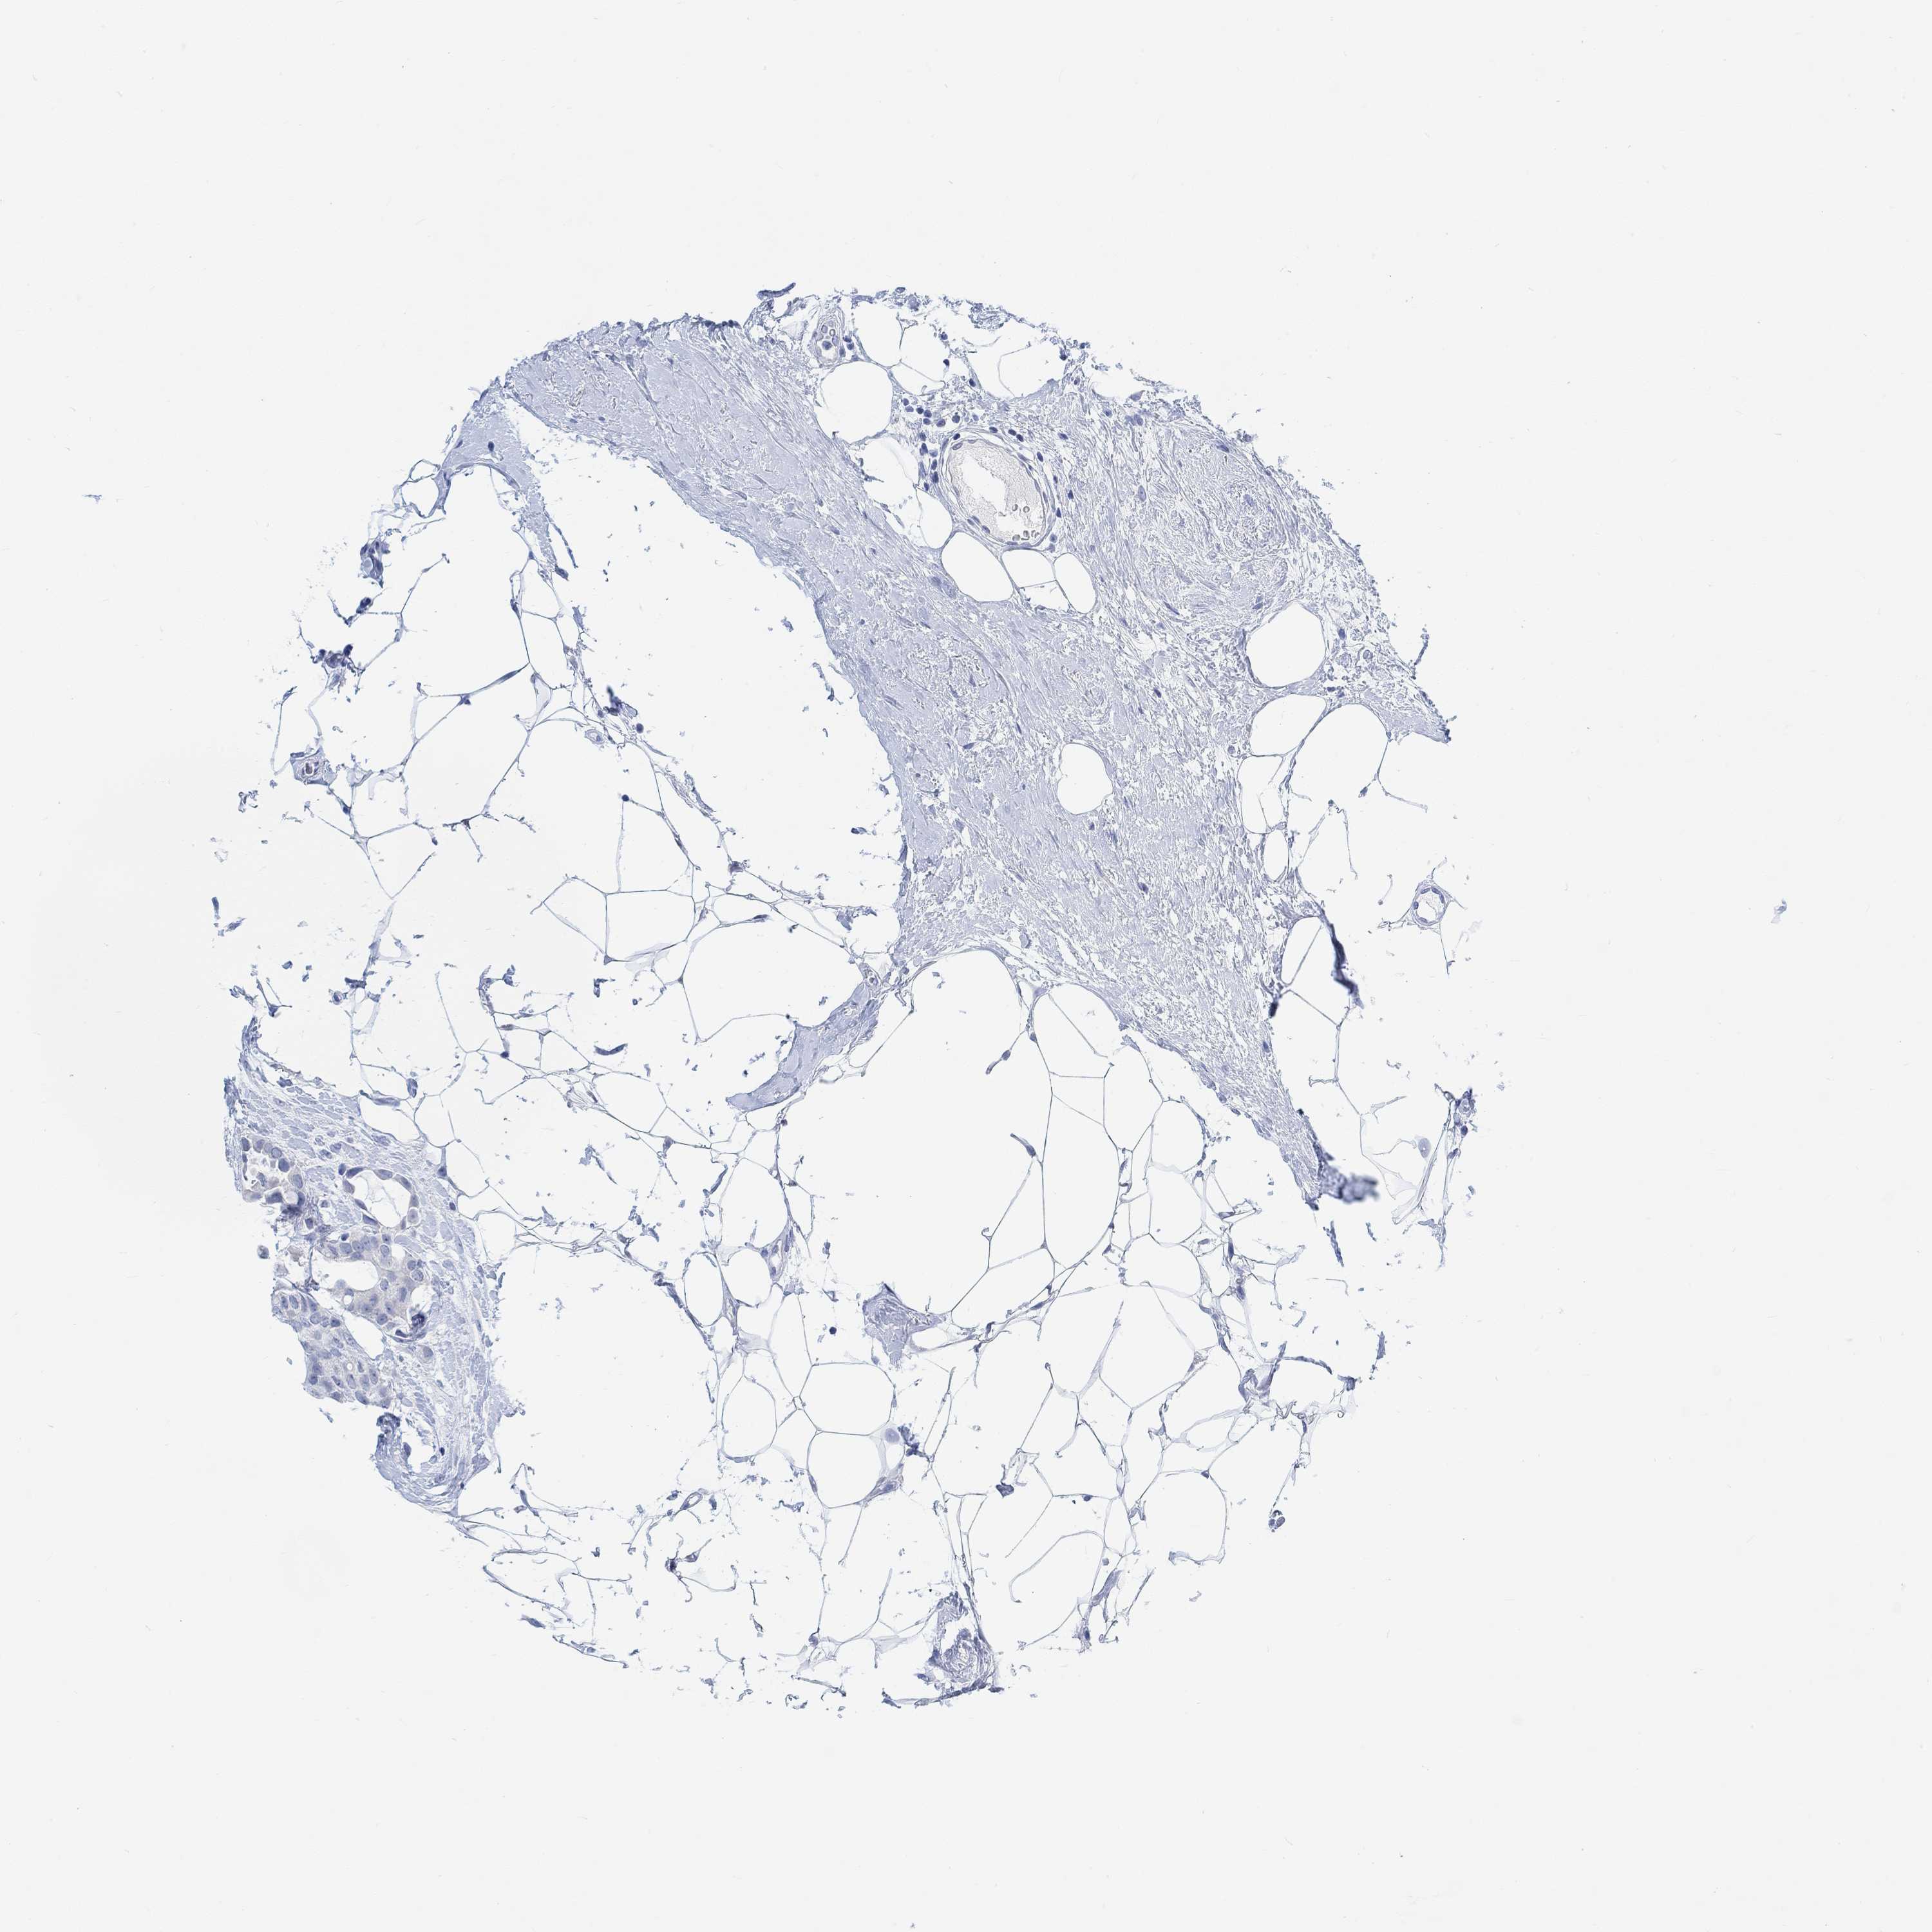

BRCA TCGA BRCA VALIDATION PROTEIN EXPRESSION

ANTIBODIES

AND

VALIDATION